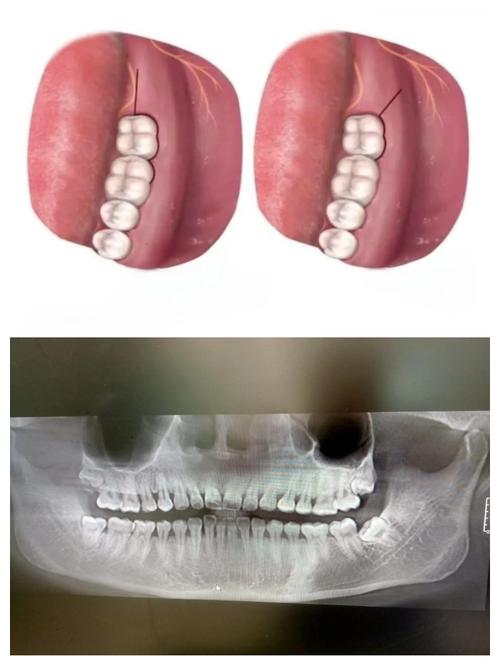

- 诊断确认: 通过临床检查(叩诊、扪诊、松动度)、X线片(根尖片、CBCT)明确诊断为不可复性牙髓炎或根尖周炎,需要根管治疗。

- 前磨牙: 通常在牙合面中央窝或偏颊/舌侧,找到发育沟或牙尖顶点。

- 磨牙:

- 第一磨牙: 通常在近中颊尖和舌尖之间的发育沟下方(近中根管口常在此区域),远中根管口在远中窝或发育沟下方。

- 第二磨牙: 变异较大,但通常遵循类似第一磨牙的规律,注意寻找发育沟。